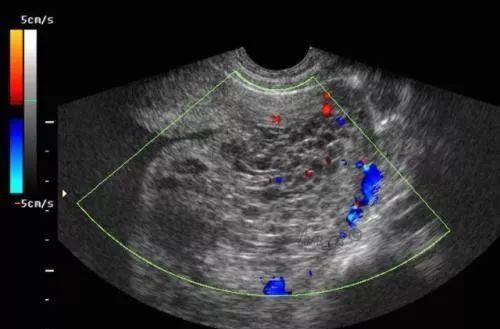

我院妇科依托张红平专家工作站成功救治一位葡萄胎患者

图片尺寸950x585